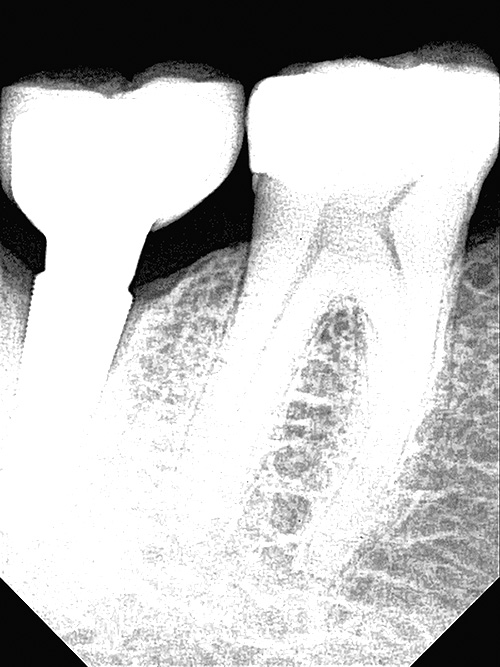

OPTEO Sensor – Klinische Bildgalerie

Ultra-HD Bildqualität – 18,5 Mikron Präzision Außergewöhnlich klare und detaillierte intraorale Bildgebung.

Ein hochwertiger dentaler intraoraler Sensor

Ultra-HD-Bildqualität für perfekte Zahnfilme.

18,5 Mikron Auflösung.